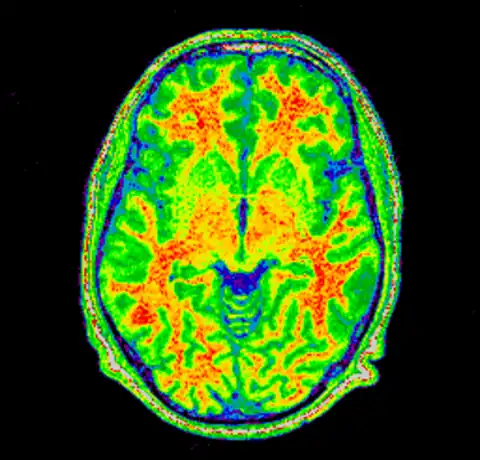

And then for completeness sake, here are the original and corrected image using a spectral colormap to better visualise the change. Note that in the second (corrected) image the intensity of the white matter is more uniform (the red part).